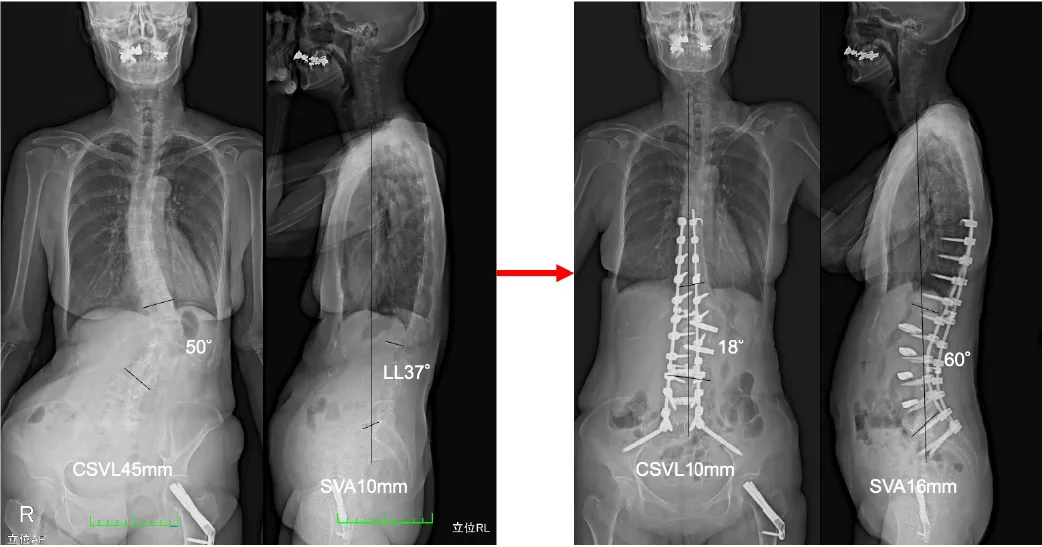

成人脊柱変形

老化に伴い背骨の後弯(前に曲がる)や側弯(横に曲がる)に伴う腰背部の痛み、歩行障害、下肢の痛みやしびれ、消化器症状、見た目の変形などさまざまです。

治療法:大きな手術が必要になりますので、2回に分けて手術を行います。入院期間は手術の方法・術後のリハビリによって異なりますが、2〜4週間程度です。

脊柱変形手術